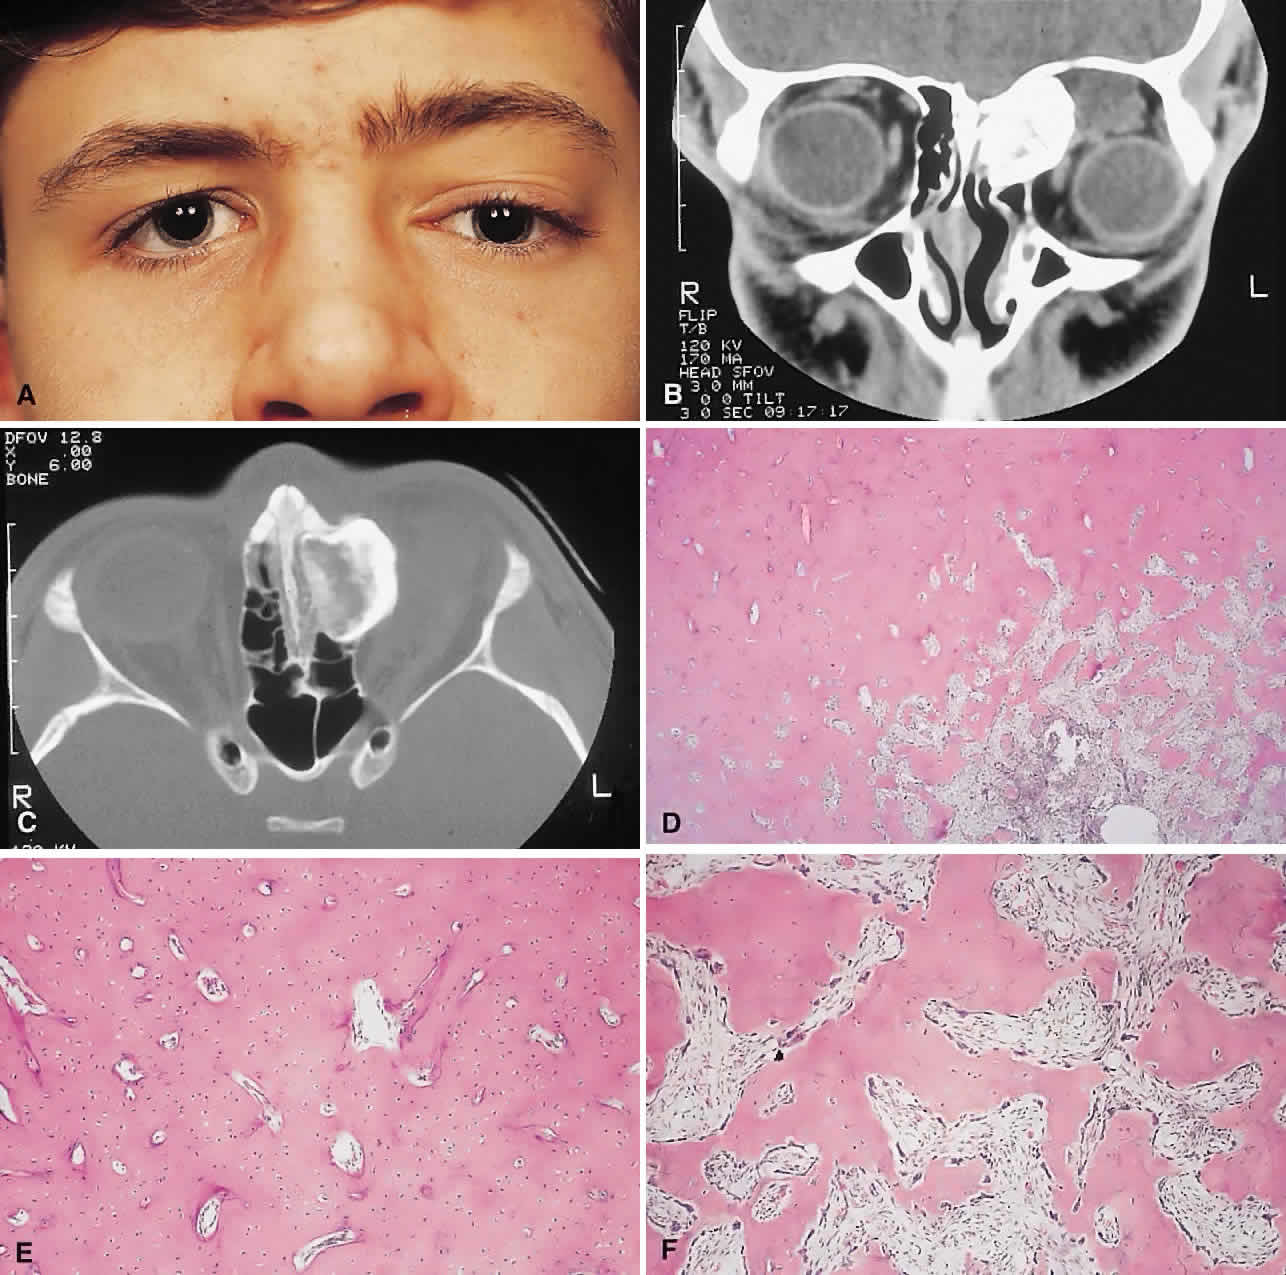

PRESENTATION. The site and the extent of disease are the major determinants of symptomatology. Facial asymmetry, proptosis, and globe displacement evolving over many years are the most common manifestations (Fig. 2). Nasolacrimal duct blockage, diplopia, nasal obstruction, malocclusion, raised intracranial pressure, and cranial nerve palsies also occur.25,28–30 Acute or subacute compressive optic neuropathy can arise as a result of intralesional hemorrhage, sphenoidal mucocele, or secondary aneurysmal bone cyst.31 A more chronic visual loss, although less commonly reported, may occur as a result of compression in the optic canal or at the chiasm. On occasion, a superimposed ischemic neuropathy in the context of chronic compression leads to an acute on chronic deterioration in vision.32

Fig. 2. A. A 20-year-old man presented with a longstanding history of left proptosis and facial asymmetry. B and C. Bone window CT scan showed extensive fibrous dysplasia involving the greater wing of the sphenoid in a sclerotic fashion and a more pagetoid appearance in the maxillary and ethmoidal regions. D and E. Dominant histologic features consisted of irregular trabeculae of woven bone in a fibrous stroma with minimal osteoblastic activity (E) surrounding the osteoid (hematoxylin-eosin; D × 20, E × 50).

This clinical spectrum is reflected in our experience of 10 cases. Changes in facial contour (7 patients), proptosis (7), globe dystopia (6), and decreased vision (3) were the major signs. Interestingly, seven patients also had pain, either localized to the orbit or described as a diffuse ipsilateral headache.

IMAGING. In the craniofacial bones, fibrous dysplasia tends to expand the bone, with thinning of the overlying cortex. The margins are poorly defined, and the dysplasia transgresses suture lines; the proportion of mineralized to fibrous tissue determines the degree of radiolucency. Most cases demonstrate a relatively equal mixture, resulting in a pagetoid appearance. Where the fibrous element is predominant, there may be cystlike areas; a preponderance of mineralized tissue, however, results in a homogeneous, sclerotic, “ground-glass” picture. Fries34 reviewed 39 patients with fibrous dysplasia of the craniofacial bones and found a pagetoid pattern to be most common (56%), followed by sclerotic (23%) and cystlike (21%) appearances.

HISTOPATHOLOGY. Macroscopically, fibrous dysplasia consists of gritty, white-to-pink tissue, often with blood or serous-filled cystic areas. Histologically, there is a fibrous background containing trabeculae of woven bone. The stroma has variable amounts of collagen, fibroblasts, and vascularity. There may also be myxomatous areas and secondary aneurysmal bone cysts. The curvilinear bone trabeculae take on a variety of configurations, including C or Y shapes (so-called Chinese characters). These trabeculae sometimes have irregular margins as a result of the attachment of collagen fibers arising in the stroma. Cartilaginous nodules as well as small foci of lamellar bone are occasionally seen, but the vast majority of lesions contain immature woven bone. At its periphery, fibrous dysplasia permeates normal bone, and there may be areas of reactive bone with more prominent lamellar bone formation and osteoblastic rimming. Sequential biopsies of fibrous dysplasia from childhood to adult life have shown that the histologic picture does not change with time.36